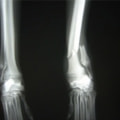

ペルシャ猫 11ヶ月齢 雄

他院にて左大腿骨遠位の成長板骨折(salter-harrisⅠ型)が認められており、治療相談を目的として来院。当院にて、キルシュナーワイヤーを用いたピンニングにより骨折部位の整復を行いました。術後の経過は良好で、現在も経過観察中です。

術前レントゲン